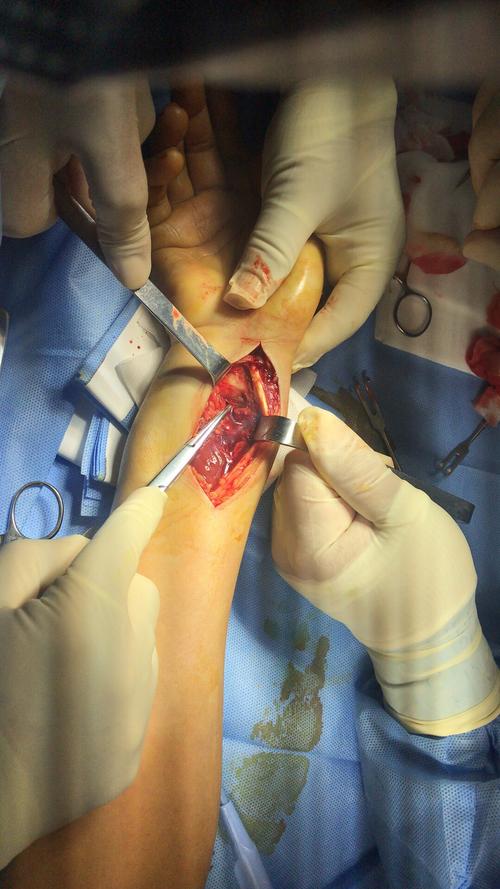

左桡骨远端骨折切开复位钢板螺钉内固定术